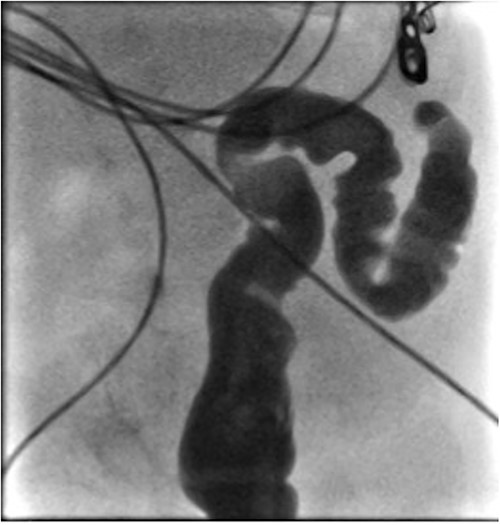

He presented at 6 weeks of age with circulatory shock requiring inotropic support and a short history of sudden abdominal distension and non bilious vomiting. He had been having regular episodes of SVT, all self limiting. Laparotomy demonstrated malrotation and a 540°midgut volvulus with extensive bowel necrosis. A fulcrum of ileum was densely adherent to the descending colon. Following intestinal resection he was left with 40 cm of small bowel from the duodenojejunal flexure, 2 cm of distal ileum and an intact colon. Following recovery from this acute episode he was managed for intestinal failure. A contrast enema was performed 10 days later in advance of stoma closure to examine the area of descending colon to which the ileum had been adherent at laparotomy. This demonstrated failure of passage of contrast proximal to the mid descending colon consistent with acquired colonic atresia (Fig. 1). Due to ongoing high stoma output and inability to progress enteral feeds, the infant proceeded to laparotomy, closure of jejunostomy, resection of colonic atresia, and anastomosis at 3 months of age. Macroscopic evidence of the atresia was encountered (Fig. 2). Histology reported a narrow calibre colon to either side of the atresia with fibrotic submucosa, focal fibrovascular proliferation, and clusters of giant cells. He subsequently achieved enteral autonomy.

Contrast enema showing failure of passage of contrast beyond descending colon.

Intra-operative photograph of acquired colonic atresia in descending colon consistent with radiological findings in Fig. 1.